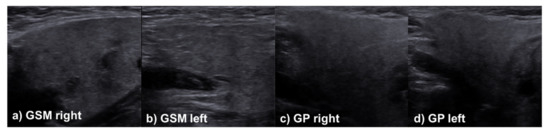

2.3. Sonographic Evaluation